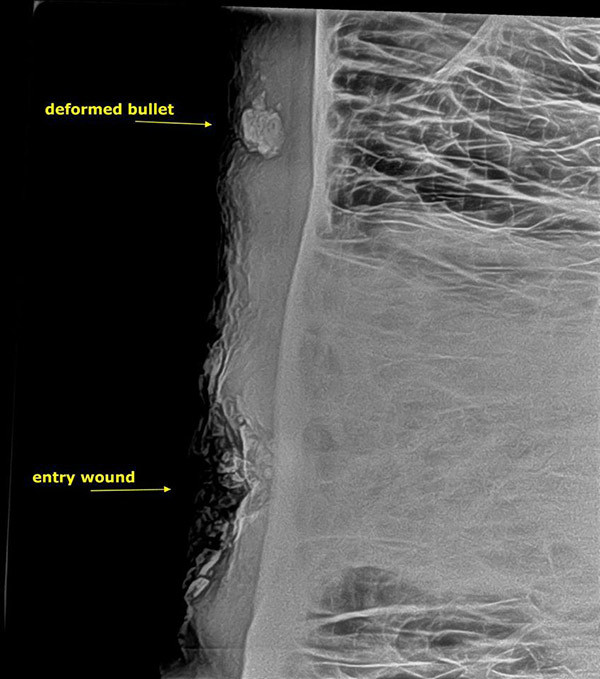

Filin röntgeni çekildiğinde ne kadar şanslı olduğu görüldü.

Kurşun bir santim aşağıya isabet etse fil anında ölecekti.